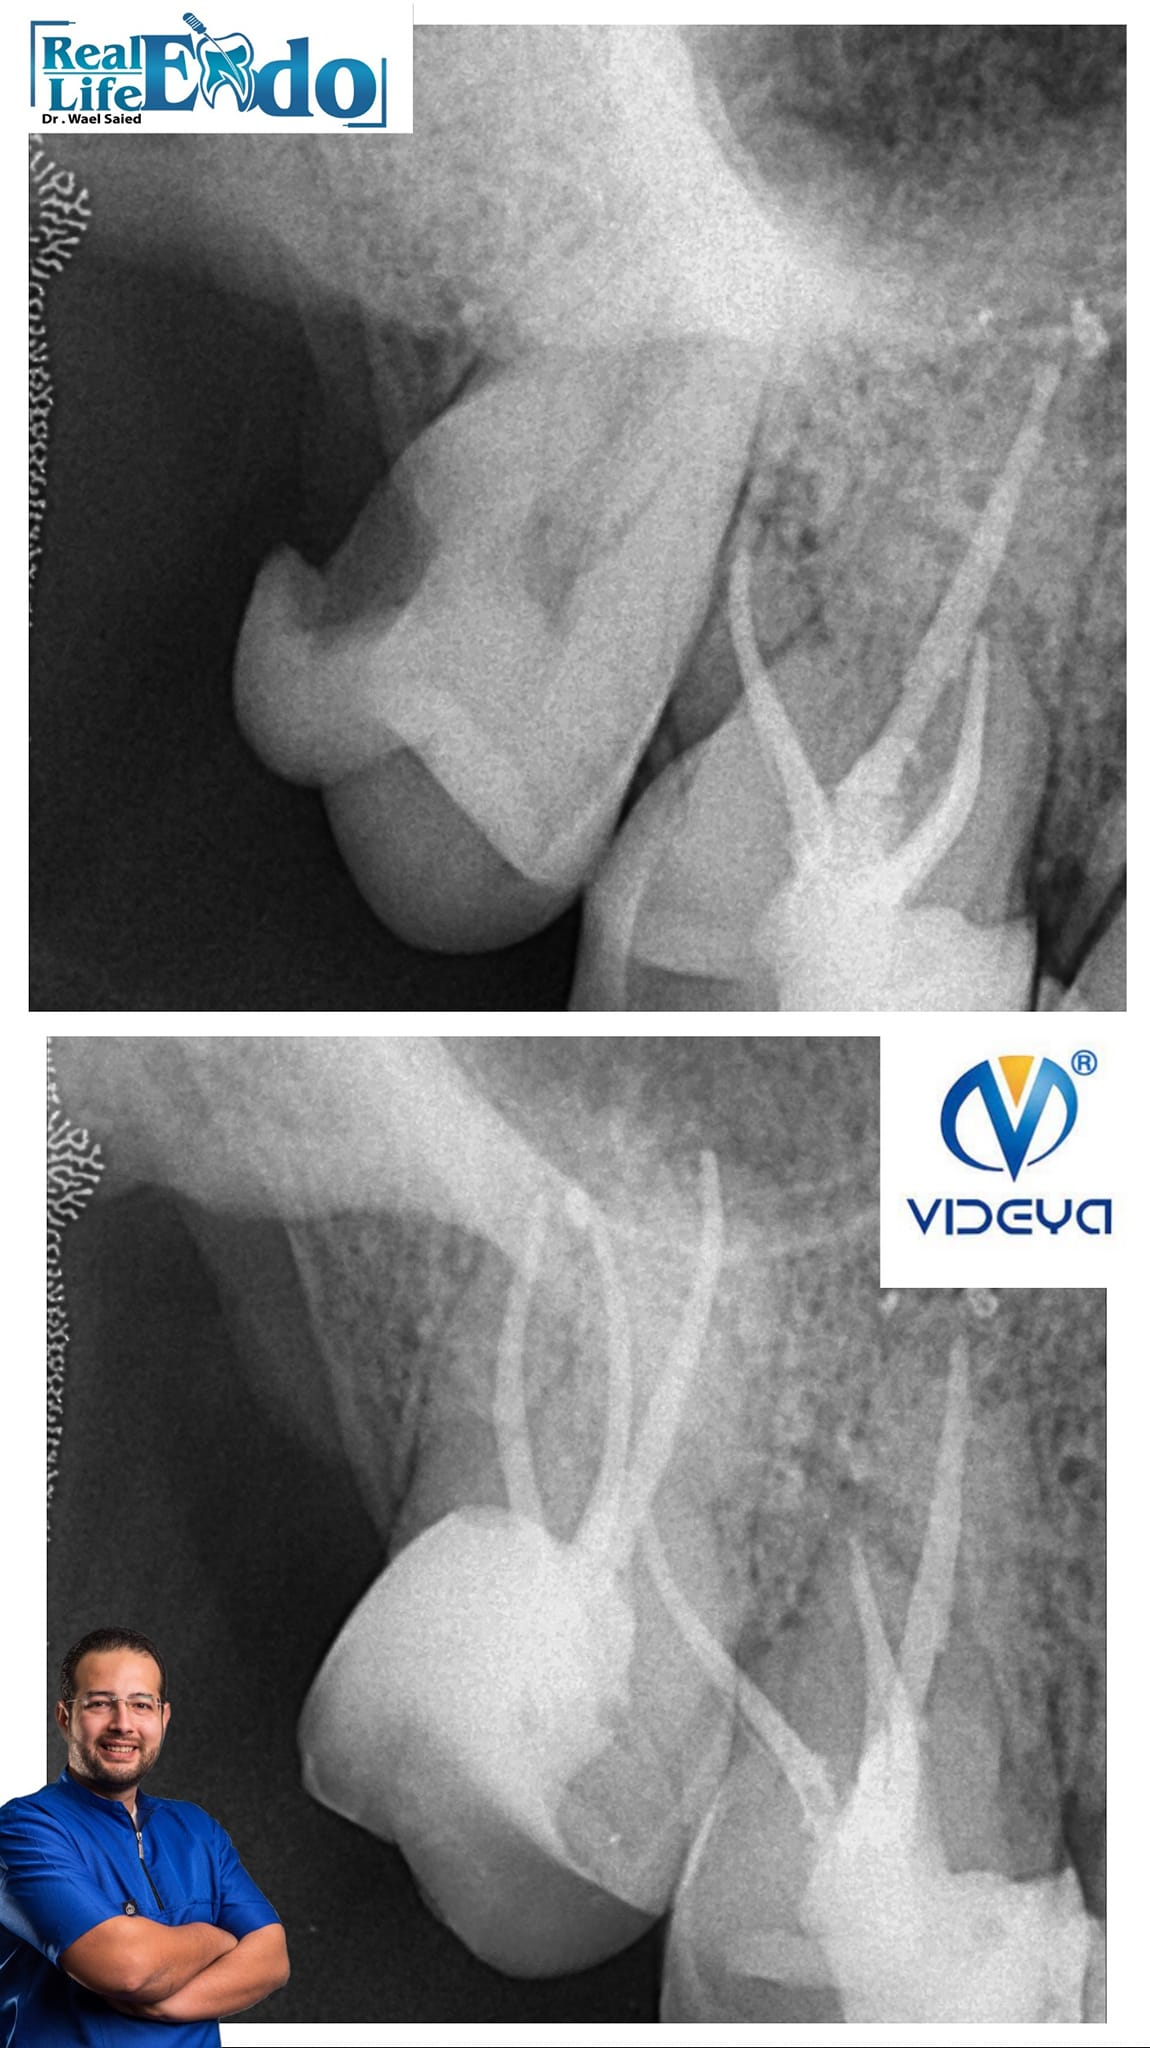

Irreversible pulpitis in upper 2nd Molar with deep distal caries in limited mouth opening patient with working length 23-24 mm..

The mouth opening was too limited that i couldn't take a master cone xray...